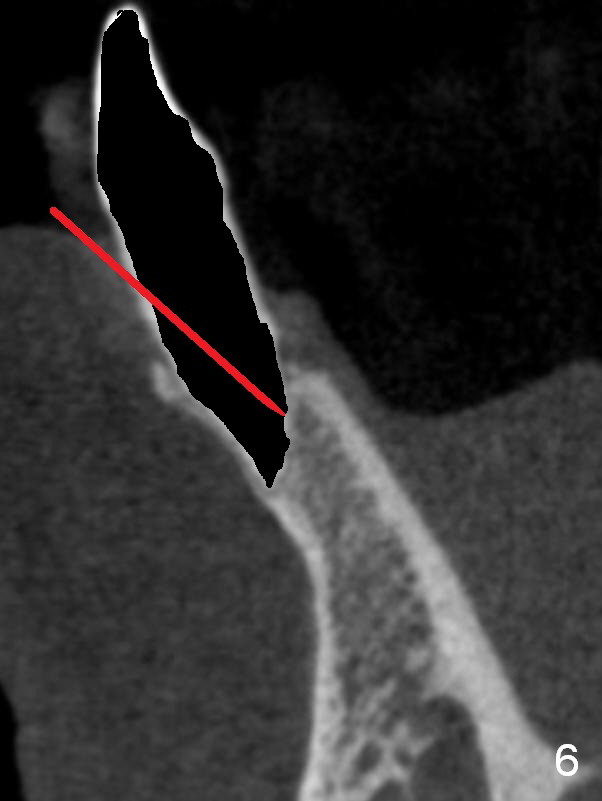

A 74-year-old man has several missing teeth (Fig.1).  His 1st goal is to replace the lower left lateral incisor (Fig.2).  The residual root has an apical lesion (Fig.3 *).  To describe intraop findings, a CT image of a different patient is used (Fig.4 coronal section; B: buccal; L: lingual).  After extraction, the buccal plate is found to be thin and low (Fig.5 arrowheads).  A 1.5 mm pilot drill (Fig.6 red line) is used to initiate osteotomy in the lingual plate of the socket.  Once the drill penetrates the lingual plate, the trajectory changes and the depth is 17 mm from the gingival margin (Fig.7).  A PA is taken (Fig.8); it appears that the osteotomy can be extended more apically.  When the pilot drill extends to 20 mm, there is sudden empty feeling.  The lingual plate has perforated (Fig.9).  A new osteotomy is established buccally (Fig.10 pink).  To avoid buccal plate perforation, especially in the buccal undercut area (>), the coronal end of the drill has to be tilted buccally (<--).  An angled abutment (3x20 mm, 15°) is placed (Fig.11,12).  The abutment is modified (Fig.13,14) to accommodate an immediate provisional (Fig.15,16 P).  Perio dressing is to be applied to prevent the bone graft from getting dislodged buccally (Fig.15).  The dressing is in place 7 days postop (Fig.17).